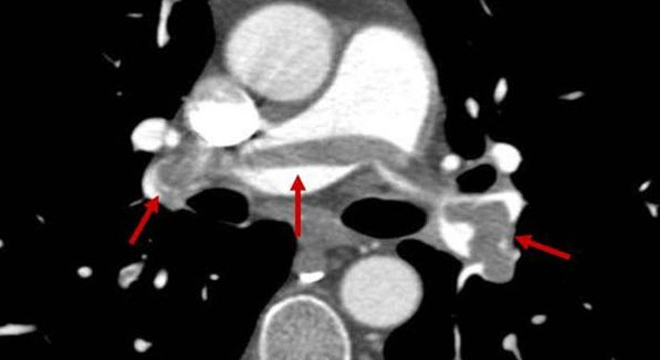

• Spiral-CT (spezielle Computertomographie zur Darstellung der Lungengefässe, bei Verdacht auf Lungenembolie relativ schnell indiziert